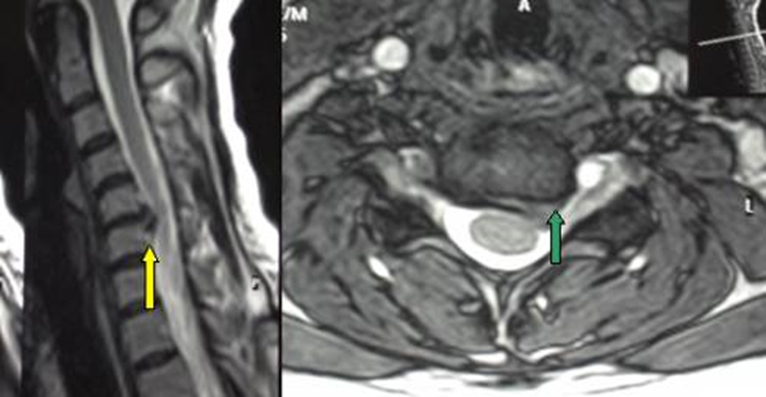

Hình 1. Thoát vị đĩa đệm cổ C5-C6 chèn ép rể C6 bên trái